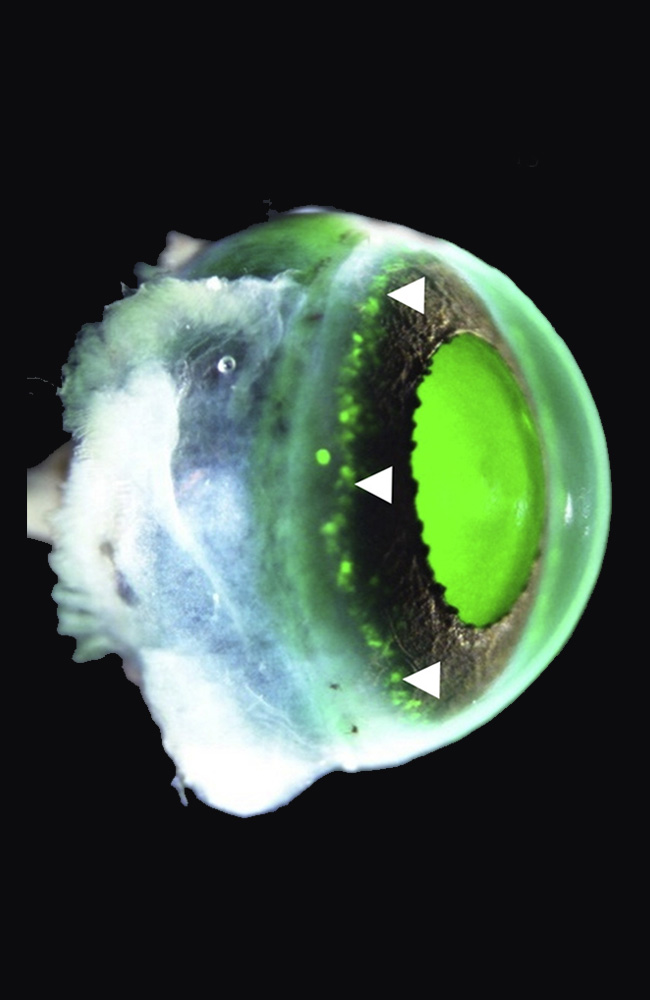

En 2024, el equipo del oftalmólogo Koji Nishida en la Universidad de Osaka anunció en The Lancet el primer ensayo clínico con láminas de epitelio corneal derivadas de iPSC alogénicas. Cuatro pacientes, cuatro ojos. La intervención consistía en trasplantar una capa de células corneales generadas a partir de un banco de iPSC compatibles con el sistema inmunitario de cada receptor.

El procedimiento era delicado. Las láminas, finas como un pétalo, se colocaban sobre la córnea dañada tras eliminar el tejido enfermo. A partir de ahí, el éxito dependía de la integración del nuevo epitelio, de su capacidad para mantenerse transparente y de no provocar rechazo.

Los resultados fueron tan sorprendentes como prudentes. En los cuatro pacientes, la superficie se reconstruyó de forma estable. La opacidad disminuyó, la inflamación se redujo y la agudeza visual mejoró. En uno de los casos, el efecto se mantuvo solo parcialmente al cabo de un año, lo que subraya la necesidad de seguimiento. Pero la seguridad del procedimiento quedó demostrada: ningún evento adverso grave, ninguna proliferación anómala, ningún tumor.